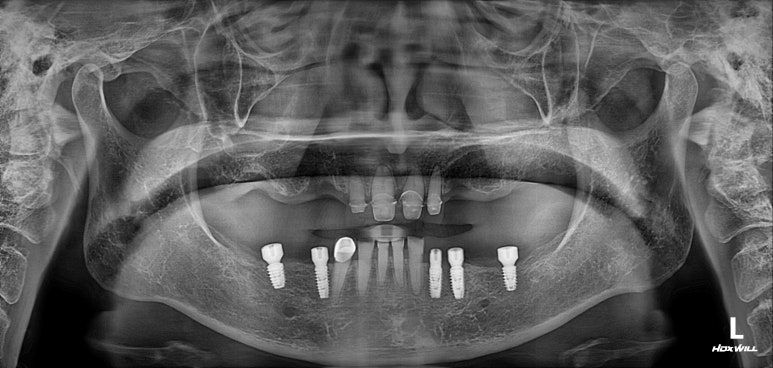

엑스레이 또한 빼놓을 수 없죠!!

적절한 위치에 심어진 임플란트는 곧 적절한 임플란트 크라운으로 이어지게 되고,

당연히 모양도 예쁘게 제작되겠지만, 음식물이 끼는 것도 최소화됩니다.

너무너무 뿌듯한 증례였습니다. 함께 고생했던 환자분께 감사의 말씀 전합니다.